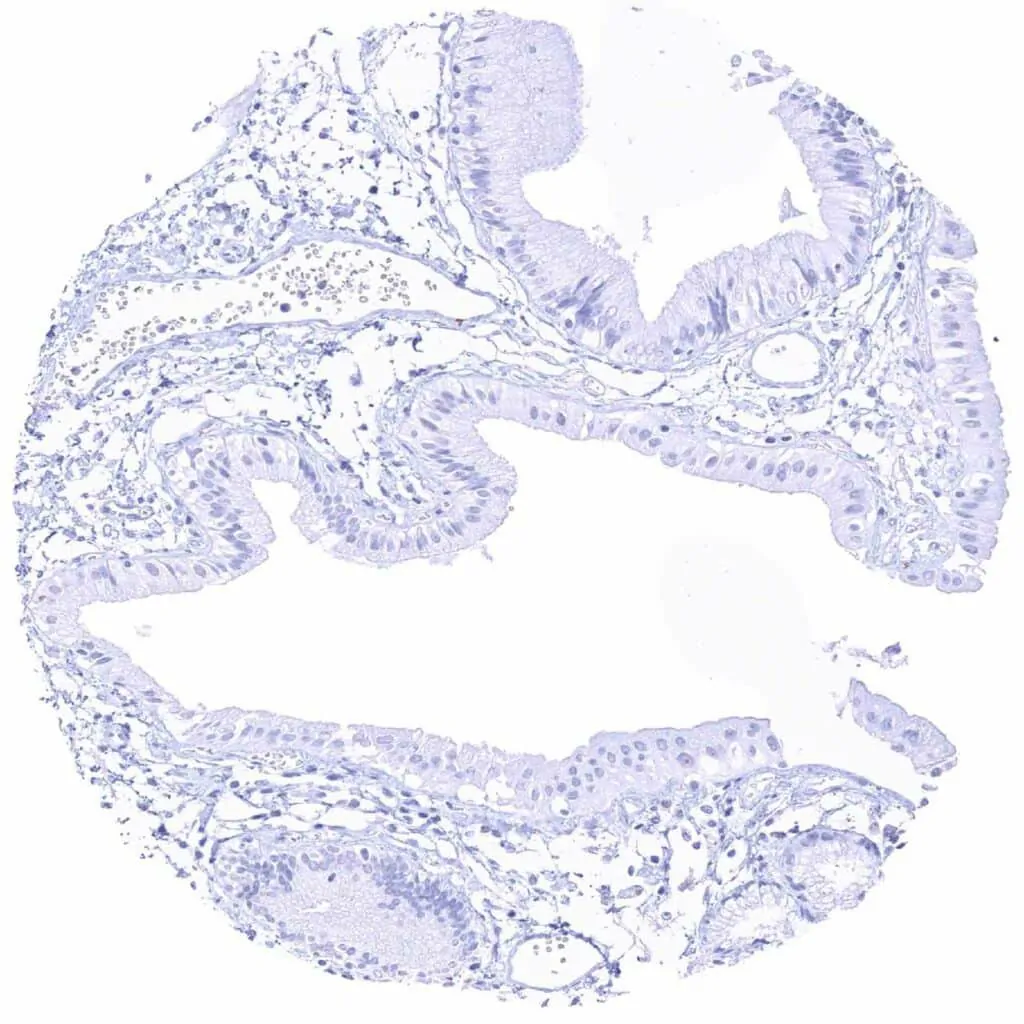

Fallopian tube, mucosa